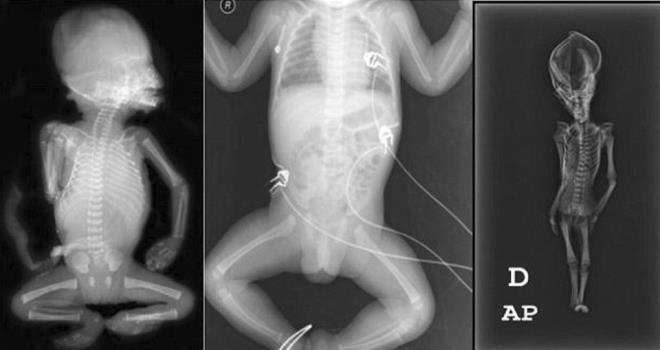

1. 2003 yılında Şili’de bulunan ve bir uzaylıya ait olabileceği iddia edilen, 15 cm uzunluğundaki mumyanın bugüne kadar tanımlanamayan çeşitli genetik hastalıklardan muzdarip cüce bir kız çocuğunun bedeni olduğu ortaya çıktı.

2. 2003 yılında, Şili’deki Atacama bölgesinde, deri bir çanta içerisinde terk edilmiş bir kilisede bulunan, koni şeklindeki bir başa ve 15 cm uzunluğa sahip mumyanın bir uzaylıya ait olabileceği iddia edilmişti.

3. İspanyol bir koleksiyoncu tarafından satın alınarak ortaya çıkarılan mumya ile ilgili daha önce Sirius isimli bir belgesel çekilmiş, çeşitli komplo teorilerinin yanı sıra bulunan iskeletin uzaylıların varlığına kanıt olabileceği öne sürülmüştü.

4. California Üniversitesi, San Francisco Üniversitesi ve Stanford Üniversitesi tarafından “Ata” ismi verilen mumyaya yapılan DNA analizleri, ,gizemini uzun süre koruyan kalıntının, çeşitli genetik mutasyonlara uğramış, 6-8 yaşında olduğu tahmin tahmin edilen cüce bir kız çocuğuna ait olduğunu ortaya koydu. Yapılan bilimsel çalışmalar, çocuğun 40 yıl önce öldüğünü ve bugüne kadar tanımlanmamış olan gen bozukluklarına sahip olduğunu açığa çıkardı.

6. Kaliforniya Üniversitesi’nden Sanchita Bhattacharya, “Ata'nın DNA'sında hepsinde zarar görmüş olan 64 gen varyantı bulduğunu” bildirerek, bunların 10 tanesinin “kısa boy” ve 11’inin “çift kaburga”ya neden olan iskelet problemleriyle ilintili olduğunu söyledi.

7. Bhattacharya, kıkırdak dokular için kullanılan kolajeni üretme sorunu yaratan ve skolyoz olarak bilinen omurganın eğriliğine neden olan genlerin de mumya içinde bulunduğunu ifade etti.    Bilim kadını, iskelet malformasyonlarının ötesinde Ata’nın, konjenital diyafram hernisi olarak bilinen bir hastalığa sahip olabileceğini de sözlerine ekledi.